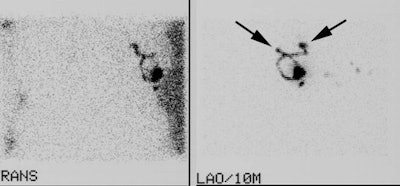

Two sentinel lymph nodes: It is important to document if there is more than one drainage track from the injection site. In the case below, LAO and transmission images demonstrate the presence of two sentinel lymph nodes (black arrows). It is very important that this finding be communicated to the surgeon. |